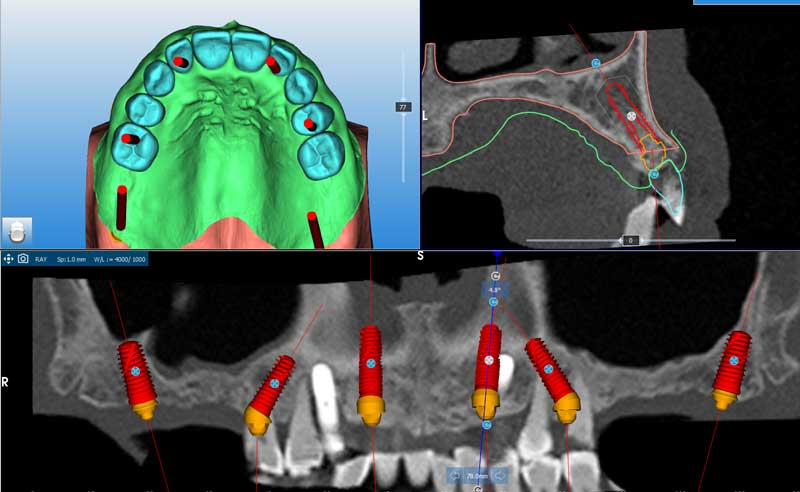

cone beam

pianificazione

Pianificazione implantare al software Real-Guide

Pianificazione implantare in trasparenza

Studio del taglio, adattamento del mascellare alla pianificazione implantare, anche in armonia della pianificazione protesica

Taglio per resettiva previsto

Visione del mascellare con resettiva effettuato, e progettazione protesica